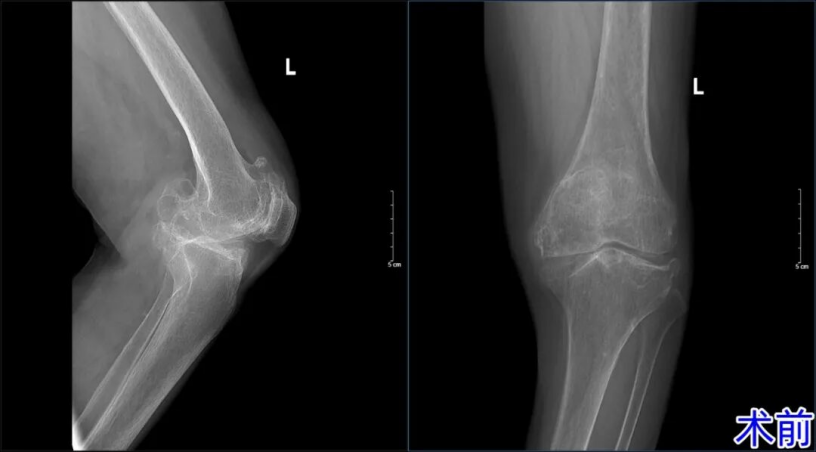

然而,左膝的隐患并未随之而去。随着疼痛日益加剧、关节严重变形,老人连基本的日常行走都举步维艰。“右腿好了,左腿绝不能拖后腿!”怀着对健康的渴望,王奶奶毫不犹豫地再次将信任交给了骨二科。面对左膝高达30°的内翻畸形、仅10°-100°的屈伸活动度,杨学良主任带领团队开启了新一轮的技术攻坚。从全面的心肺功能评估到假体的精确选型,从微创切口的设计到截骨角度的测算,每一个环节都精雕细琢,力求完美。